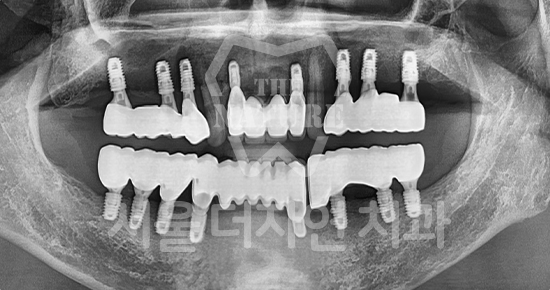

#Maxillary Bone Grafting

-

BEFORE: 2021.11.02

AFTER: 2022.01.19